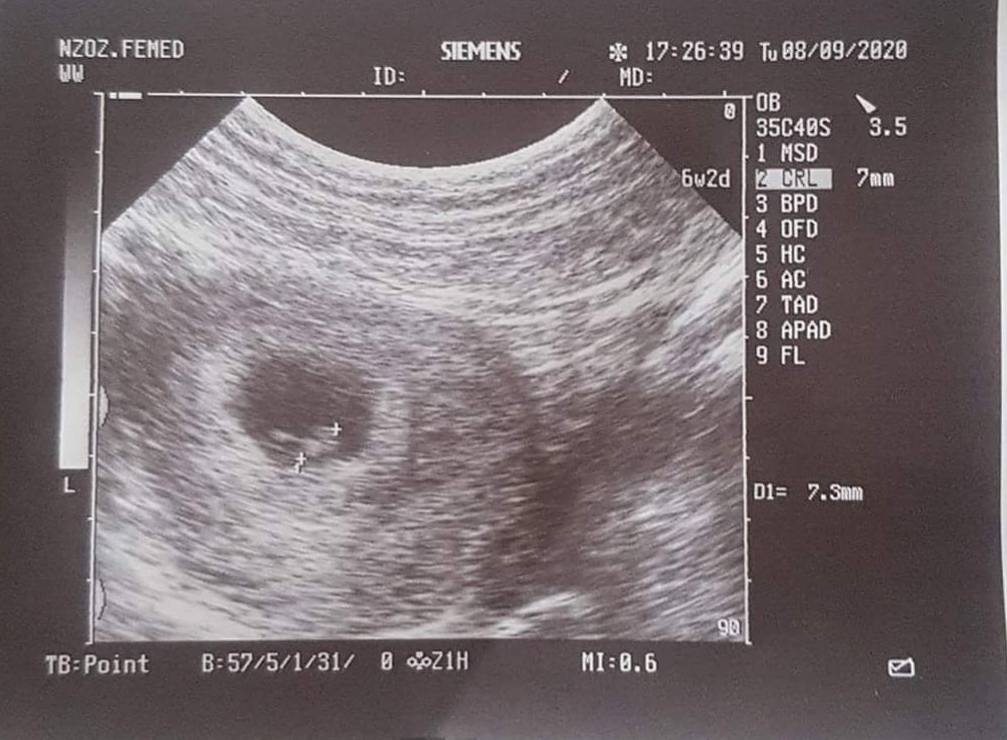

Po stracie 2 lata temu i 2 letnich staraniach zobaczyliśmy w końcu 2 kreski na teście. Dziś zaczynamy 8 tydzien A nasza sytuacja nie daje się cieszyć. Ciągły stres o to czy znów nie spotka nas tragedia. Od początku brązowe plamienia, biorę duphaston ale nic nie pomaga. 8.09 na wizycie widziałam bijące serduszko, wdg usg wtedy 6+2. Chwilę przed wizytą plamienia ustały lekarz powiedział że wszystko ok więc nawet wyleciało mi z głowy żeby zapytać. Następna wizyta dopiero 17 chyba zglupieje do tego czasu. Czy któraś miewa podobnie? Tu macie zdjęcie mojego kropka, termin na 2.05Zobacz załącznik 1174464